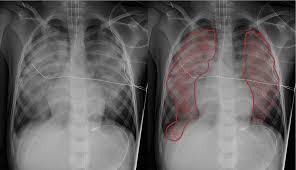

한눈에 보는 요약표

| 구분 | 주로 느끼는 증상 | 체크 포인트 |

|---|---|---|

| 폐부종(폐 안) | 갑작스런 숨참, 누우면 악화, 거품 가래 | 야간 호흡곤란, 청색증, 흉통/식은땀 동반 |

| 흉수(폐 바깥) | 서서히 심해지는 숨참, 마른기침, 한쪽 흉통 | 발열·체중감소 등 원인 관련 증상 확인 |

| 즉시 진료 신호 | 말하기 어려울 정도의 호흡곤란 | 거품/피 섞인 가래, 청색증, 의식저하 |